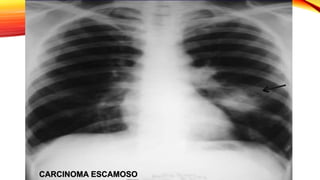

Carcinoma escamoso

• Masa central de gran tamaño que a menudo se cavita.

Carcinoma de célulaspequeñas • Localización prehiliar en el 80% y se asocia a adenopatías mediastinicas. Carcinoma escamoso • Masa central de gran tamaño que a menudo se cavita. Adenocarcinoma • Se presenta como nódulo o masa de distribución periférica y ocasional presencia de broncrograma aéreo. • Carcinoma bronquioalveolar presenta broncograma aéreo y puede presentar cavitación Farreras & Rozman Medicina Interna 17 edicion, capitulo 81, Pag 726.